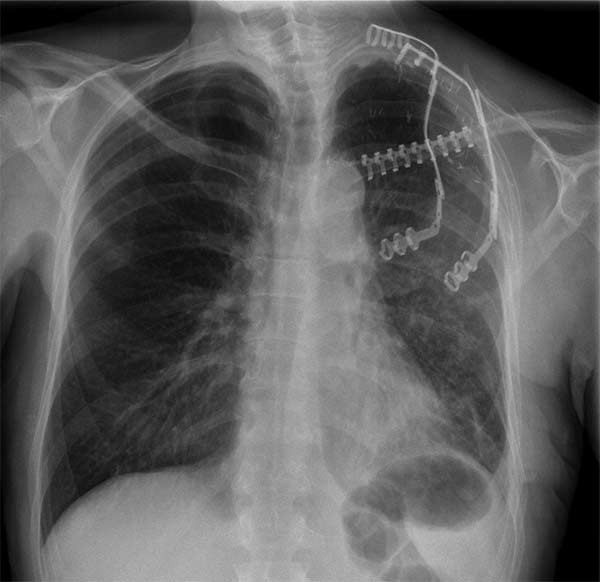

Surgery was performed with curative intent. The patient was positioned supine with the neck fully extended and the head turned away from the tumor. The tumor was approached through the anterior trans-cervical approach described by Dartevelle. This approach allowed us to dissect the subclavian vascular bundle and the nerve roots of the brachial plexus freely, quickly and safely without sacrificing the radical intent of the operation. After assessing the extent of the tumor from inside and outside of the chest, the lateral arches of the first, second and third ribs were cut and removed en-bloc with the surgical specimen (Figure 2). Due to the high risk of de-stabilizing the shoulder girdle after resection of the first three ribs, clavicle division and muscle resection, we reconstructed the chest wall and clavicle using the Stratos™ titanium bars and clips (Strasbourg Thoracic Osteosyntheses System; MedXpert, Heitersheim, Germany) (Figure 3). The chest wall defect and the reconstructed clavicle were covered with polytetrafluoroethylene (PTFE) patches (Figure 4).